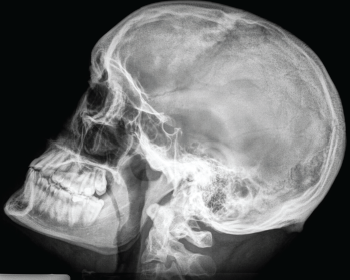

Se llama imagen médica al conjunto de técnicas y procesos usados para crear imágenes del cuerpo humano, o partes de él, con propósitos clínicos, es decir, procedimientos médicos que buscan revelar, diagnosticar o examinar enfermedades.

El Diplomado de Imagenología Diagnóstica, está dirigido a estudiantes de medicina, residentes y médicos generales, con el fin de adquirir los conocimientos, habilidades y destrezas así como las actitudes y valores propios de la práctica clínica necesarios para traducir la sintomatología de sus pacientes a partir de estudios de Imagenología en diagnósticos clínicos.

Conocer los principios básicos de radiología, así como las bases en la física y su aplicación clínica.

Comprender adecuadamente la indicación de los estudios de Imagenología para tener un enfoque diagnóstico integral.

Aprender a interpretar adecuadamente, con una metodología establecida, una radiografía de tórax normal, así como identificar los síndromes pleuropulmonares más comunes.

Identificar el uso específico de la tomografía y resonancia, así como su utilidad en el diagnóstico específico de patologías más comunes. -